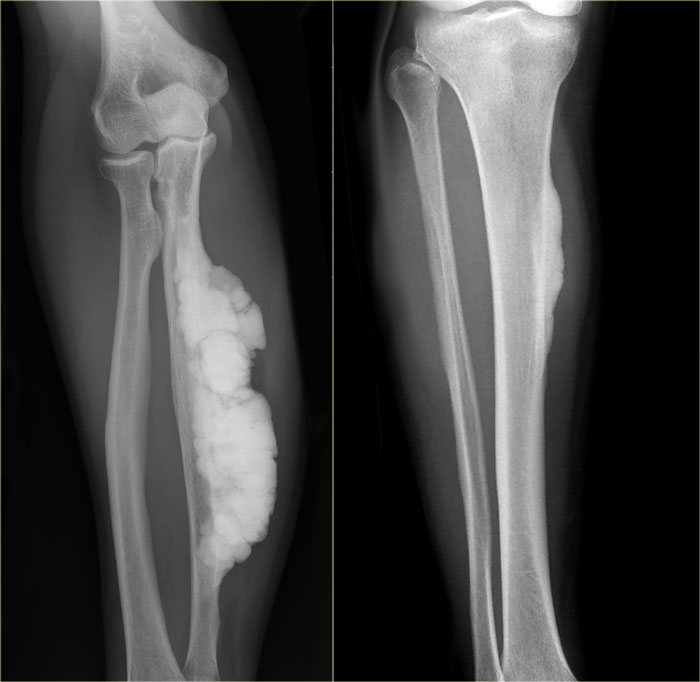

Study the image and then continue reading.

The findings are:

• A well-defined and homogeneous sclerotic mass with a broad base to the underlying diaphysis of the fibula.

A juxtacortical or parosteal osteosarcoma should be considered, particularly when a history of trauma is lacking.

Final diagnosis: parosteal osteosarcoma